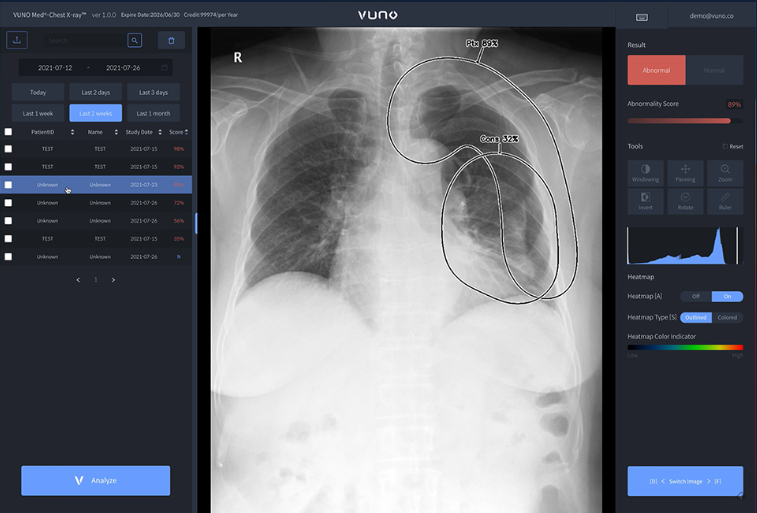

VUNO MED-Chest X-ray

흉부 X-ray 영상을 통해 비정상 소견 여부와 위치 정보를 제공해 의료진의 판독을 보조하는 소프트웨어.

간질성 음영, 경화, 결절, 기흉, 흉수의 다섯가지 소견에 대해 정상, 비정상 여부를 분석해 정보를 제공합니다.